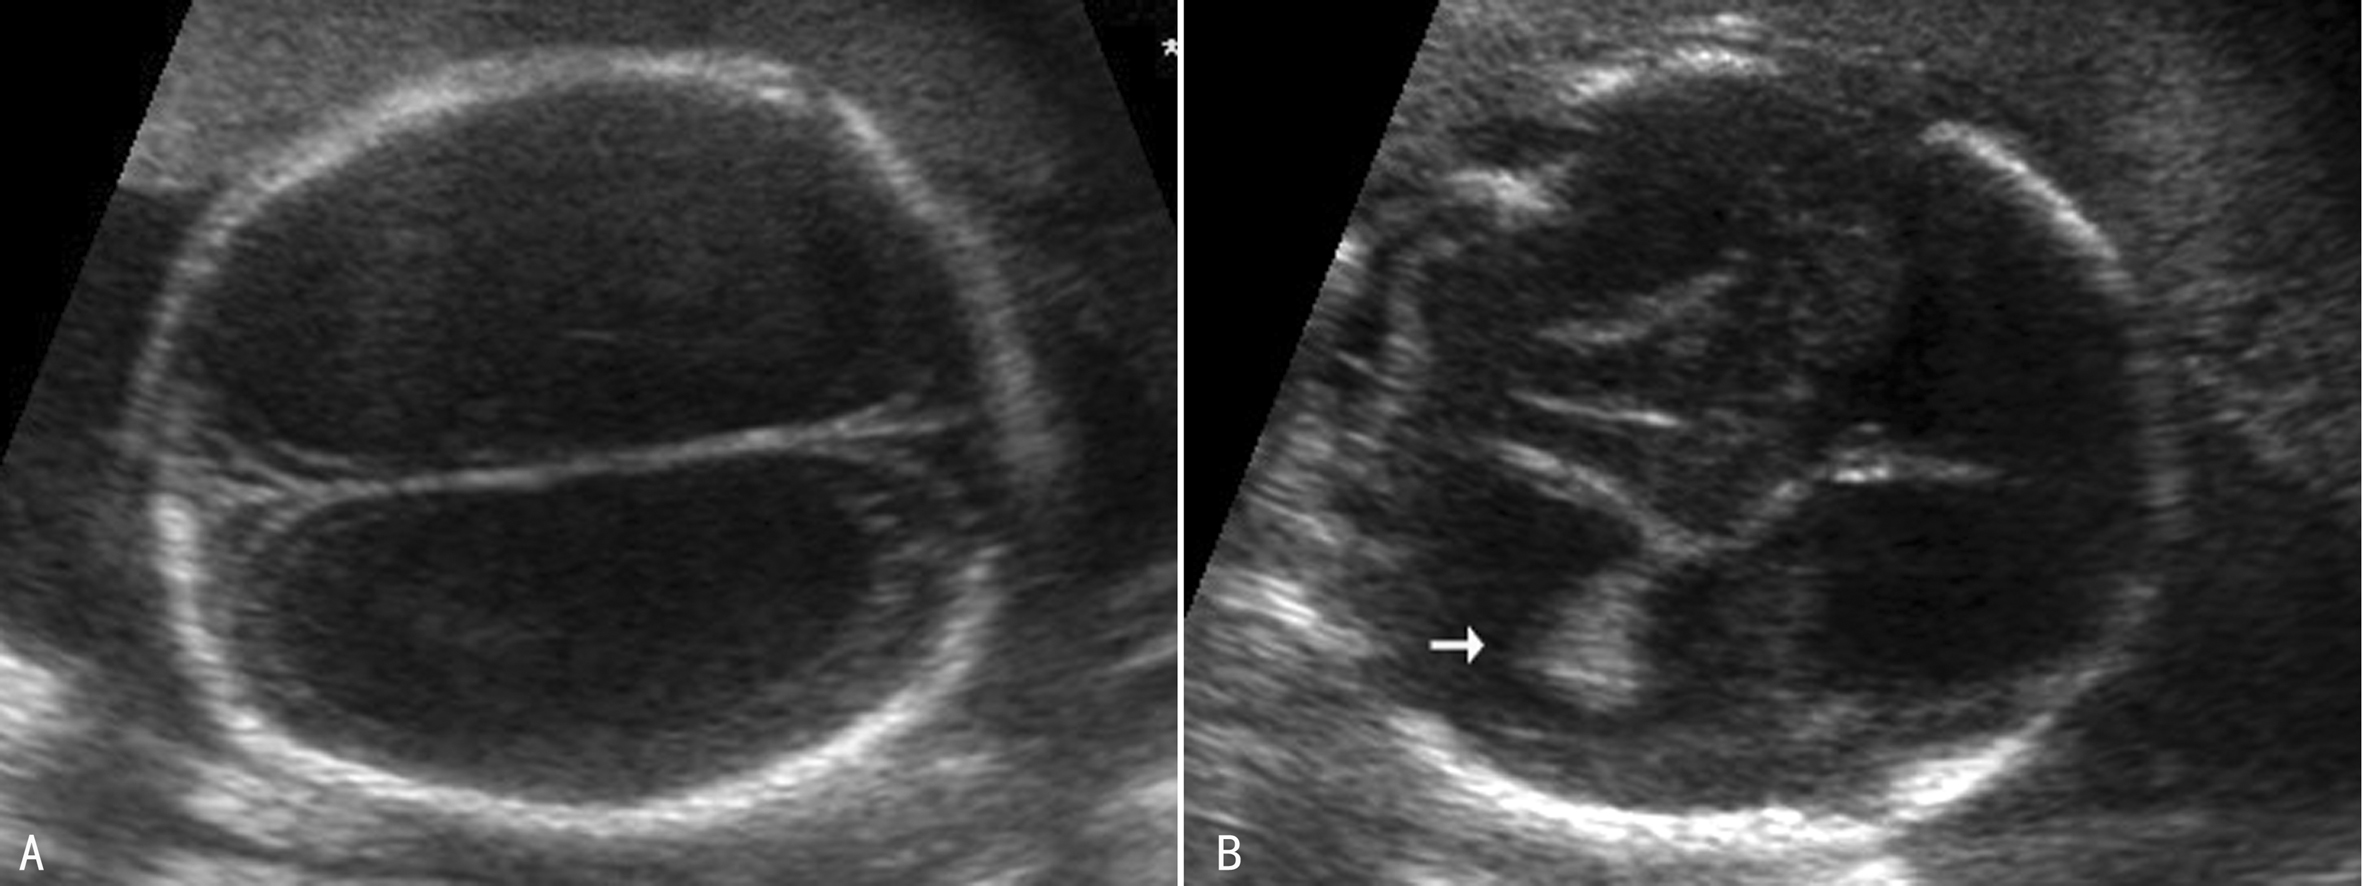

3.重度脑室增宽 重度侧脑室增宽(SVM)俗称HC(图3)。超声显像检查可以显示为对称性脑室扩张(图3,图4A),也可以显示为非对称性脑室扩张(图4B),严重时颅内完全由无回声的积液占据,脑组织显示不清。重度侧脑室增宽最常见的原因是中脑导水管硬化,并且有60%的胎儿伴有CNS结构异常,包括前脑无裂畸形、Dandy-Walker畸形、脊柱裂、小脑扁桃体下疝畸形、脑穿通畸形等,但较少合并染色体异常。超声显像检查显示胎儿头颅增大,脑室系统扩张,压力升高,脑室周围灰质、白质相继受压,严重时颅内结构不可辨认或显示不清,神经结构及功能严重受损,胎儿出生后多有严重的智力障碍。

图3胎儿脑积水声像图,剪头示脉络膜悬吊于脑室内

图4胎儿重度脑积水声像图

(2)脉络丛活动:常见于侧脑室严重增宽时,显示为脉络丛非常薄或者脉络丛自由地飘浮在脑室中(图3)。